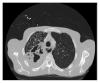

Bronchoesophageal Fistula due to Esophageal Tuberculosis

This is a case report regarding a patient who presented with 6 months of dysphagia and subsequent 40-pound weight loss. The patient underwent imaging, suggestive of pulmonary TB. Further workup of his dysphagia with esophagogastroduodenoscopy and bronchoscopy revealed two bronchoesophageal fistulas. Tuberculosis is an important differential diagnosis of prolonged dysphagia in immunocompetent patients.